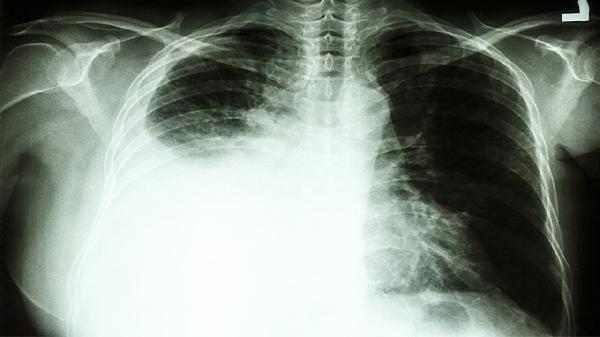

PET-CT檢查不能單獨(dú)確診肺癌,但可作為重要輔助手段。肺癌確診需結(jié)合病理活檢、支氣管鏡檢查、胸部CT增強(qiáng)掃描、腫瘤標(biāo)志物檢測(cè)、臨床表現(xiàn)等綜合判斷。

PET-CT通過顯示病灶葡萄糖代謝情況輔助判斷腫瘤性質(zhì)。惡性腫瘤通常表現(xiàn)為高代謝灶,但活動(dòng)性結(jié)核、炎性假瘤等良性病變也可能出現(xiàn)假陽性。檢查結(jié)果需結(jié)合CT影像特征分析,如分葉征、毛刺征等典型惡性征象。

組織病理檢查是肺癌診斷金標(biāo)準(zhǔn)。通過支氣管鏡活檢、經(jīng)皮肺穿刺或胸腔鏡手術(shù)獲取病變組織,進(jìn)行病理學(xué)檢查和免疫組化分析,可明確腫瘤類型及分化程度。PET-CT可幫助定位最佳活檢部位。

肺癌診斷需呼吸科、影像科、病理科等多學(xué)科協(xié)作。PET-CT提供功能代謝信息,CT提供解剖細(xì)節(jié),二者融合圖像可提升診斷準(zhǔn)確性,但最終仍需病理確診。